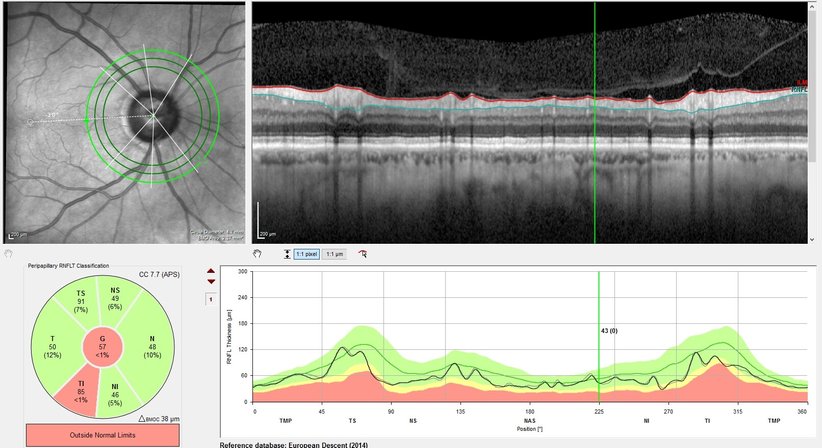

Der Begriff Grüner Star, Glaukom, umfasst Augenerkrankungen, welche – unter anderem bedingt durch einen erhöhten Augeninnendruck – den Sehnerv schädigen und bei einer unzureichenden Therapie zu einer Einengung des Blickfeldes bis hin zur Erblindung führen können. Die Verbreitung dieser Krankheit beträgt etwa 1% der Bevölkerung, wobei das Erkrankungsrisiko mit zunehmendem Alter deutlich ansteigt. Gefährlich ist vor allem der Umstand, dass sich diese Erkrankung sehr langsam und unbemerkt entwickelt und sich ein einmal eingetretener Sehschaden nicht wieder umkehren lässt. Schon ab dem 40. Lebensjahr wird deshalb eine regelmäßige Vorsorgeuntersuchung zum Zweck einer rechtzeitigen Diagnosestellung und gegebenenfalls Behandlung empfohlen. Im Falle von betroffenen Patienten in der engeren Familie wird eine Vorsorgeuntersuchung bereits früher empfohlen. Zur umfassenden Abklärung eines Glaukoms werden in unserer Ordination eine Augendruckmessung (Tonometrie), eine klinische Untersuchung des Sehnervens mittels Mikroskop, eine hochauflösenden Laser-Schichtbildaufnahme (sog. OCT, optische Kohärenz Tomographie) des Sehnervens und der Nervenfaserschicht sowie eine Gesichtsfelduntersuchung (Perimetrie) standardmäßig durchgeführt.